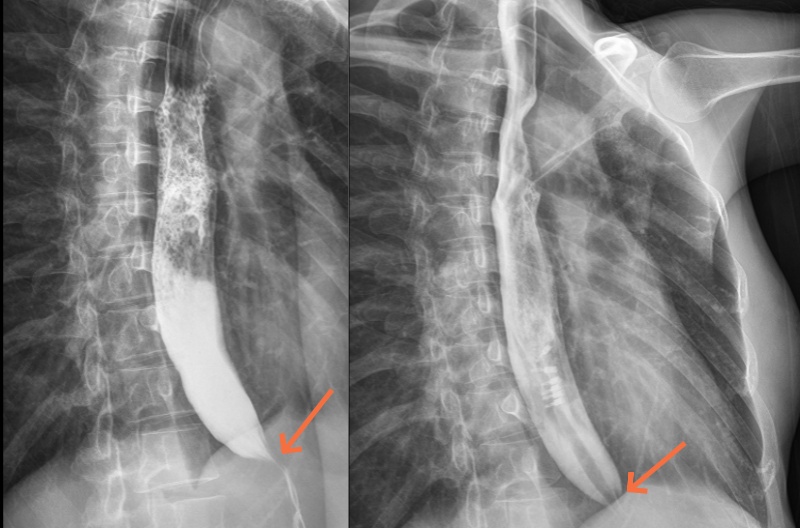

李女士手术前(左图)造影提示食管扩张,成“鸟嘴样”改变,手术后(右图)改善